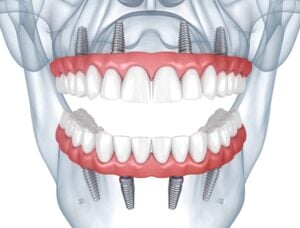

If you’re dreaming of a smile that shines and stays put without the trouble dentures can sometimes cause, All-on-4® dental implants are worth considering. This clever dental solution is especially helpful for those who’ve said goodbye to several or all of their teeth. While the term “All-on-4” is actually a trademarked name by the dental […]

Read All-on-4®: is it Right for You?